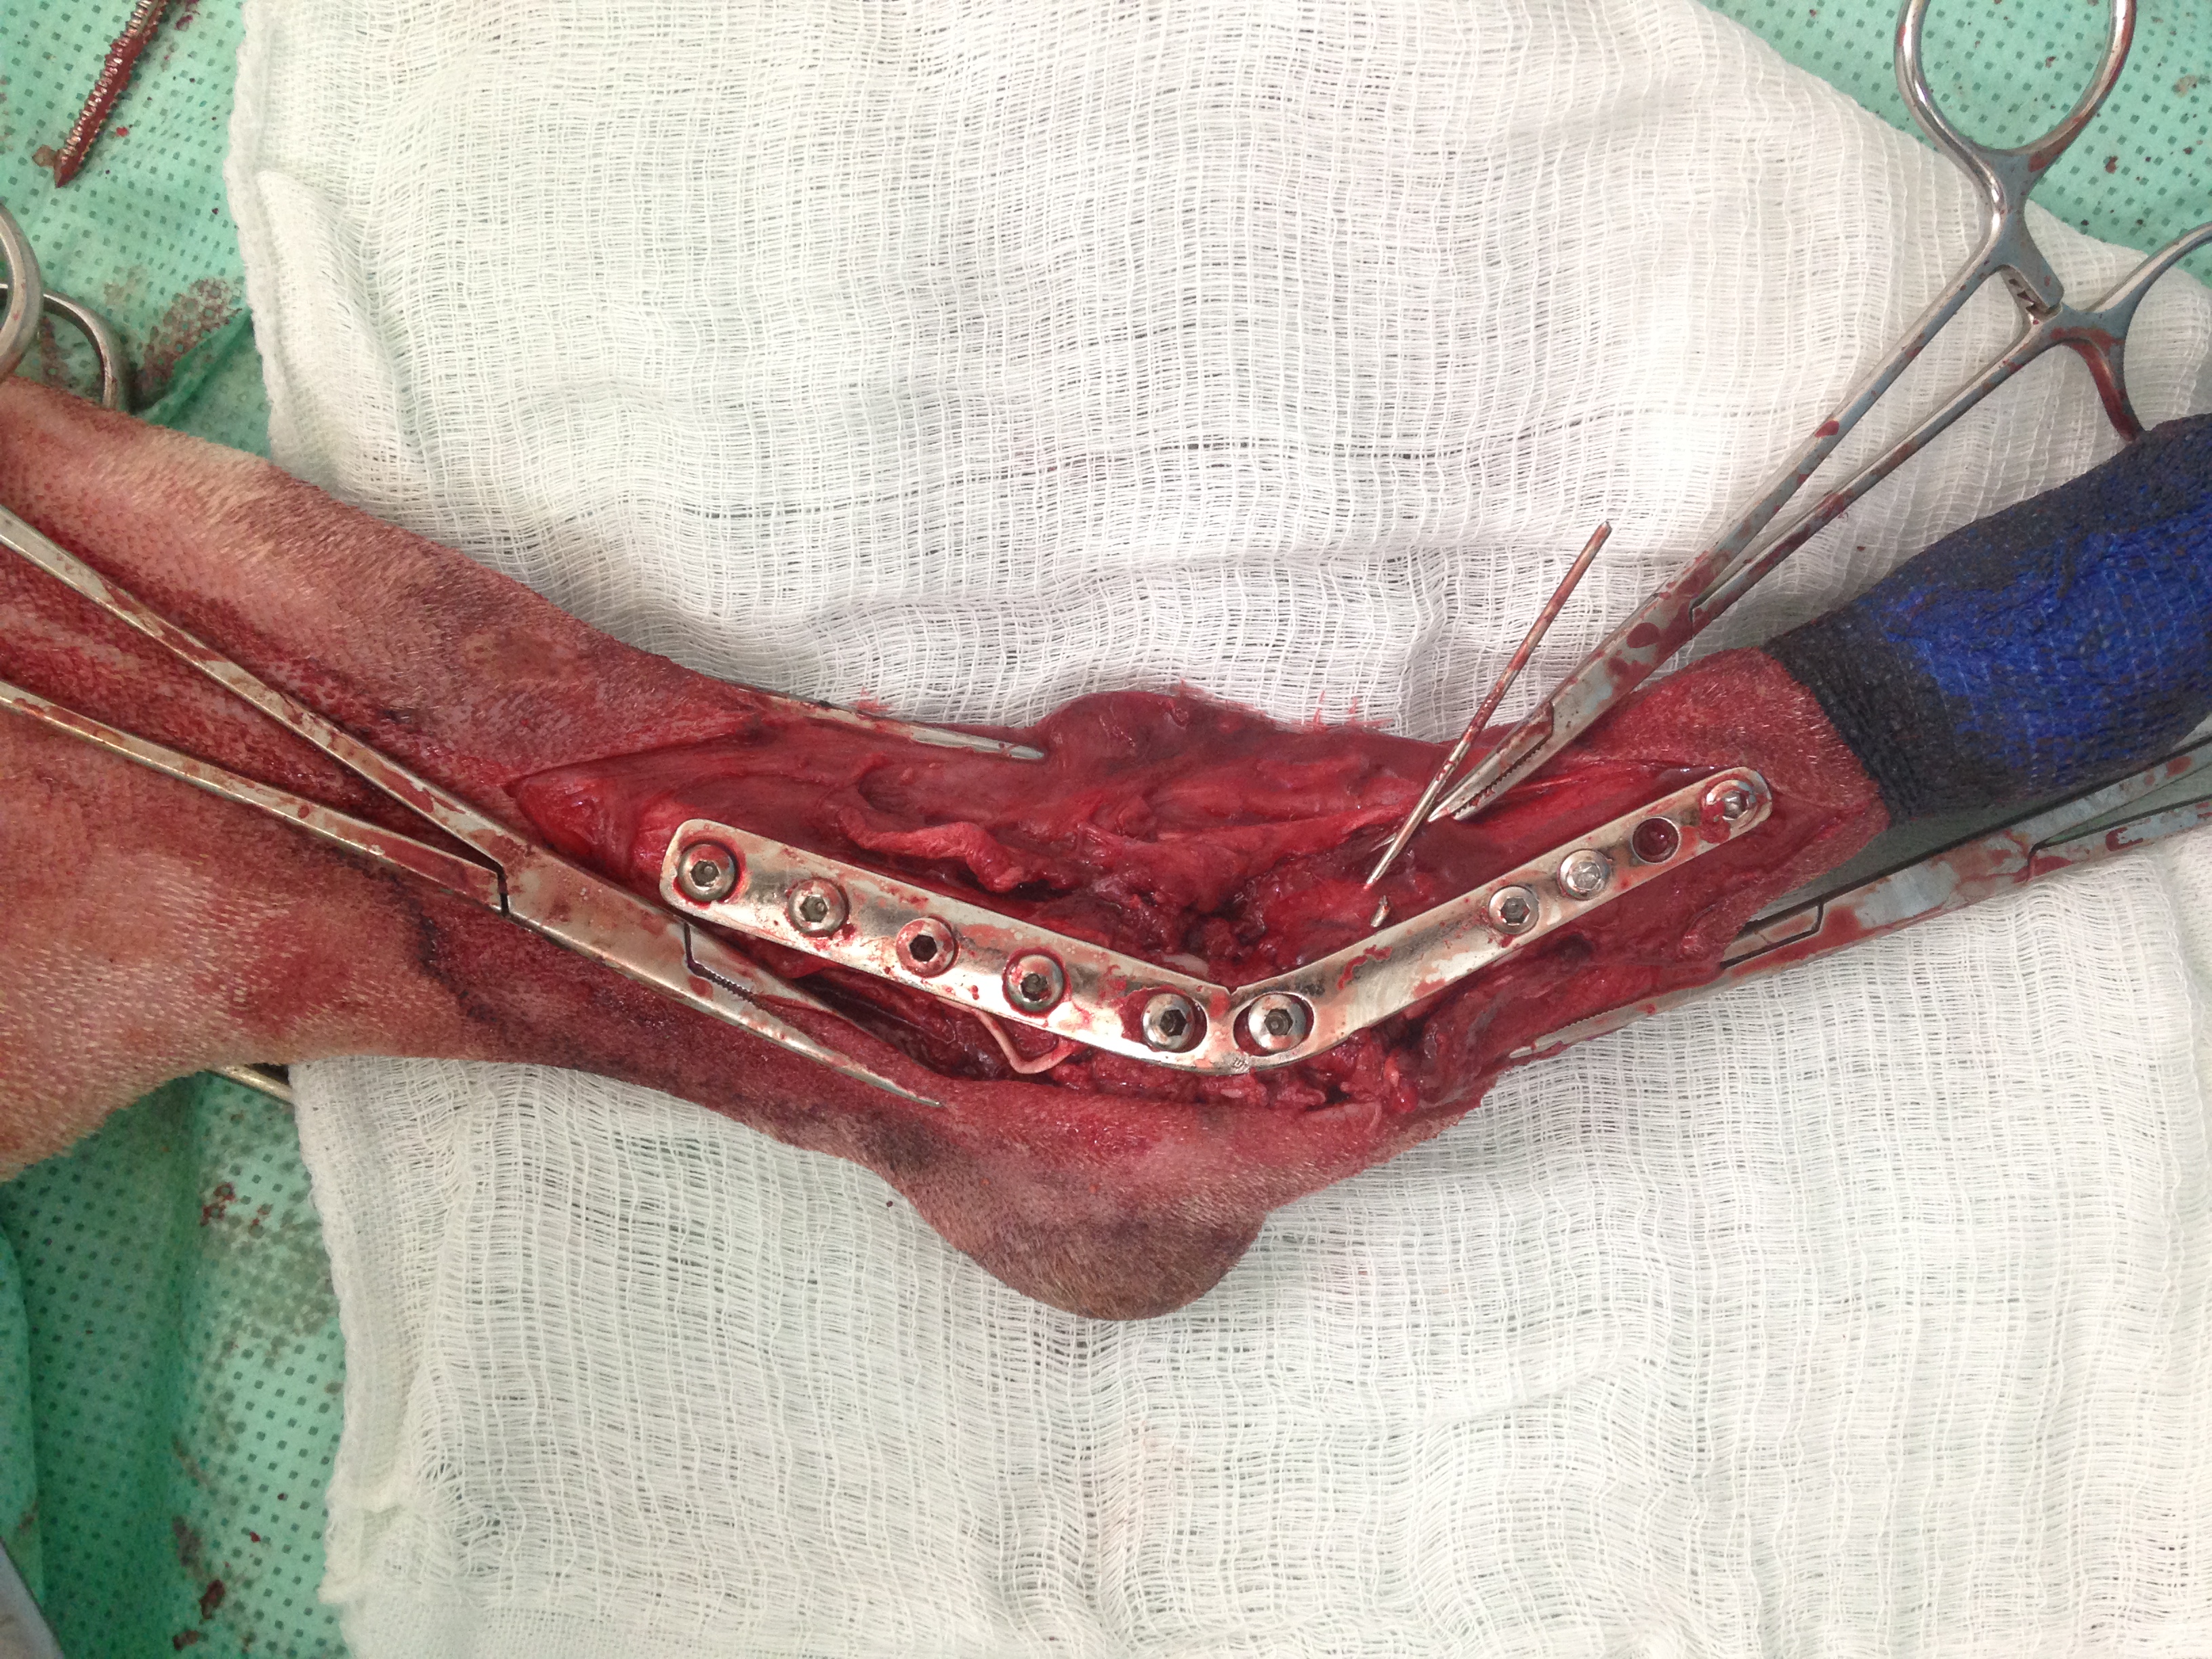

Casos Interessantes > ARTRODESE Tíbio-Tarsica por placa medial

Veja algumas Fotos